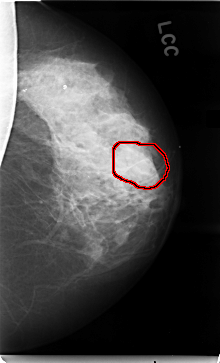

C_0017_1.LEFT_CC

LEFT_CC LINES 4712 PIXELS_PER_LINE 2856 BITS_PER_PIXEL 12 RESOLUTION 50 OVERLAY

FILE: C_0017_1.LEFT_CC.OVERLAY

TOTAL_ABNORMALITIES 1

ABNORMALITY 1

LESION_TYPE MASS SHAPE LOBULATED MARGINS ILL_DEFINED

ASSESSMENT 4

SUBTLETY 1

PATHOLOGY MALIGNANT

TOTAL_OUTLINES 1

BOUNDARY